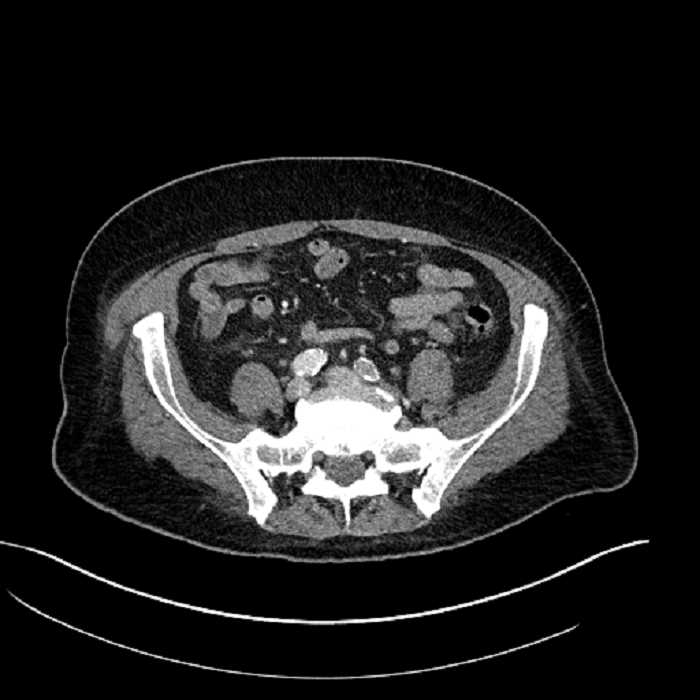

• Mild mural thickening of a segment of the sigmoid colon with adjacent fat stranding and a 1.5 cm fluid and gas collection along the tip of an inflamed diverticulum

• Loss of the normal fat plane between this collection and adjacent loops of small bowel, which demonstrate mural thickening

• No bowel obstruction

Additionally, loss of the normal fat plane between the peridiverticular collection and adjacent thickened loops of small bowel raises the potential for an enterocolonic fistula.

Hepatic abscess showing the double target sign with low density internally surrounded by a thin inner enhancing rim (red arrow) and ill-defined outer low density rim (yellow arrow). Blue arrow indicates an internal septation. Red arrows: additional smaller subcapsular abscesses. Red arrow: focal contained perforation associated with diverticulitis.